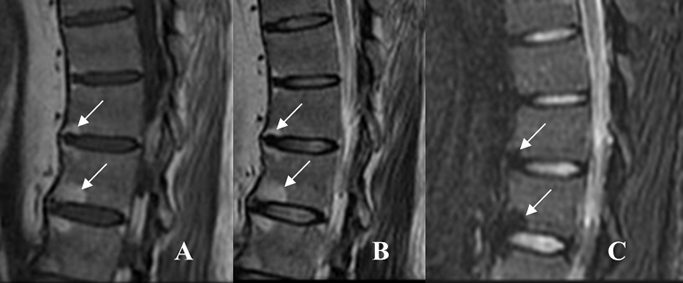

Fig 59 D. Lesiones Romanus.

A: RM sagital en T1 y B: RM sagital en T1 STIR con contraste. Lesiones en las esquinas de las vértebras, hipointensas en T1 y con realce del contraste, por lesiones Romanus de evolución aguda. En la parte anterior de L5, hay otras lesiones hiperintensas en T1 y sin realce, por depósito graso.

Fig 59 E. Lesiones Romanus.

A: RM sagital en T1 y B: RM sagital en T2. Lesiones en las esquinas de las vértebras, hiperintensas en ambas secuencias, por lesiones Romanus con depósito graso.

Fig 59 F. Espondilitis anquilosante.

A: Rx lateral. Se identifican sindesmofitos, en la parte anterior de los cuerpos vertebrales y esquinas densas.

B: RM sagital en T1 y C: RM sagital en T2. Lesiones Romanus en la parte anterior de los cuerpos vertebrales, hiperintensas en ambas secuencias, por evolución subaguda.

Fig 59 G. Lesiones Romanus.

A: RM sagital en T1, B: RM sagital en T2 y C: RM sagital en STIR. Múltiples lesiones Romanus, en las esquinas de los cuerpos lumbares. Son hiperintensas en T1 y T2 y suprimen en STIR, por depósito graso de evolución subaguda.